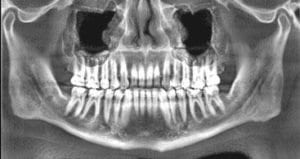

Cone Beam Computed Tomography

All navigation starts with a map. Cone Beam 3-D images provide high-definition, three-dimensional, digital data, and precise anatomical information of all oral and maxillofacial structures. These 3-D images are the map that our doctors use to plan and execute your surgical treatment. They are the key to all image guided surgery. This is done: With less radiation then conventional Medical CT. In a comfortable “open”......